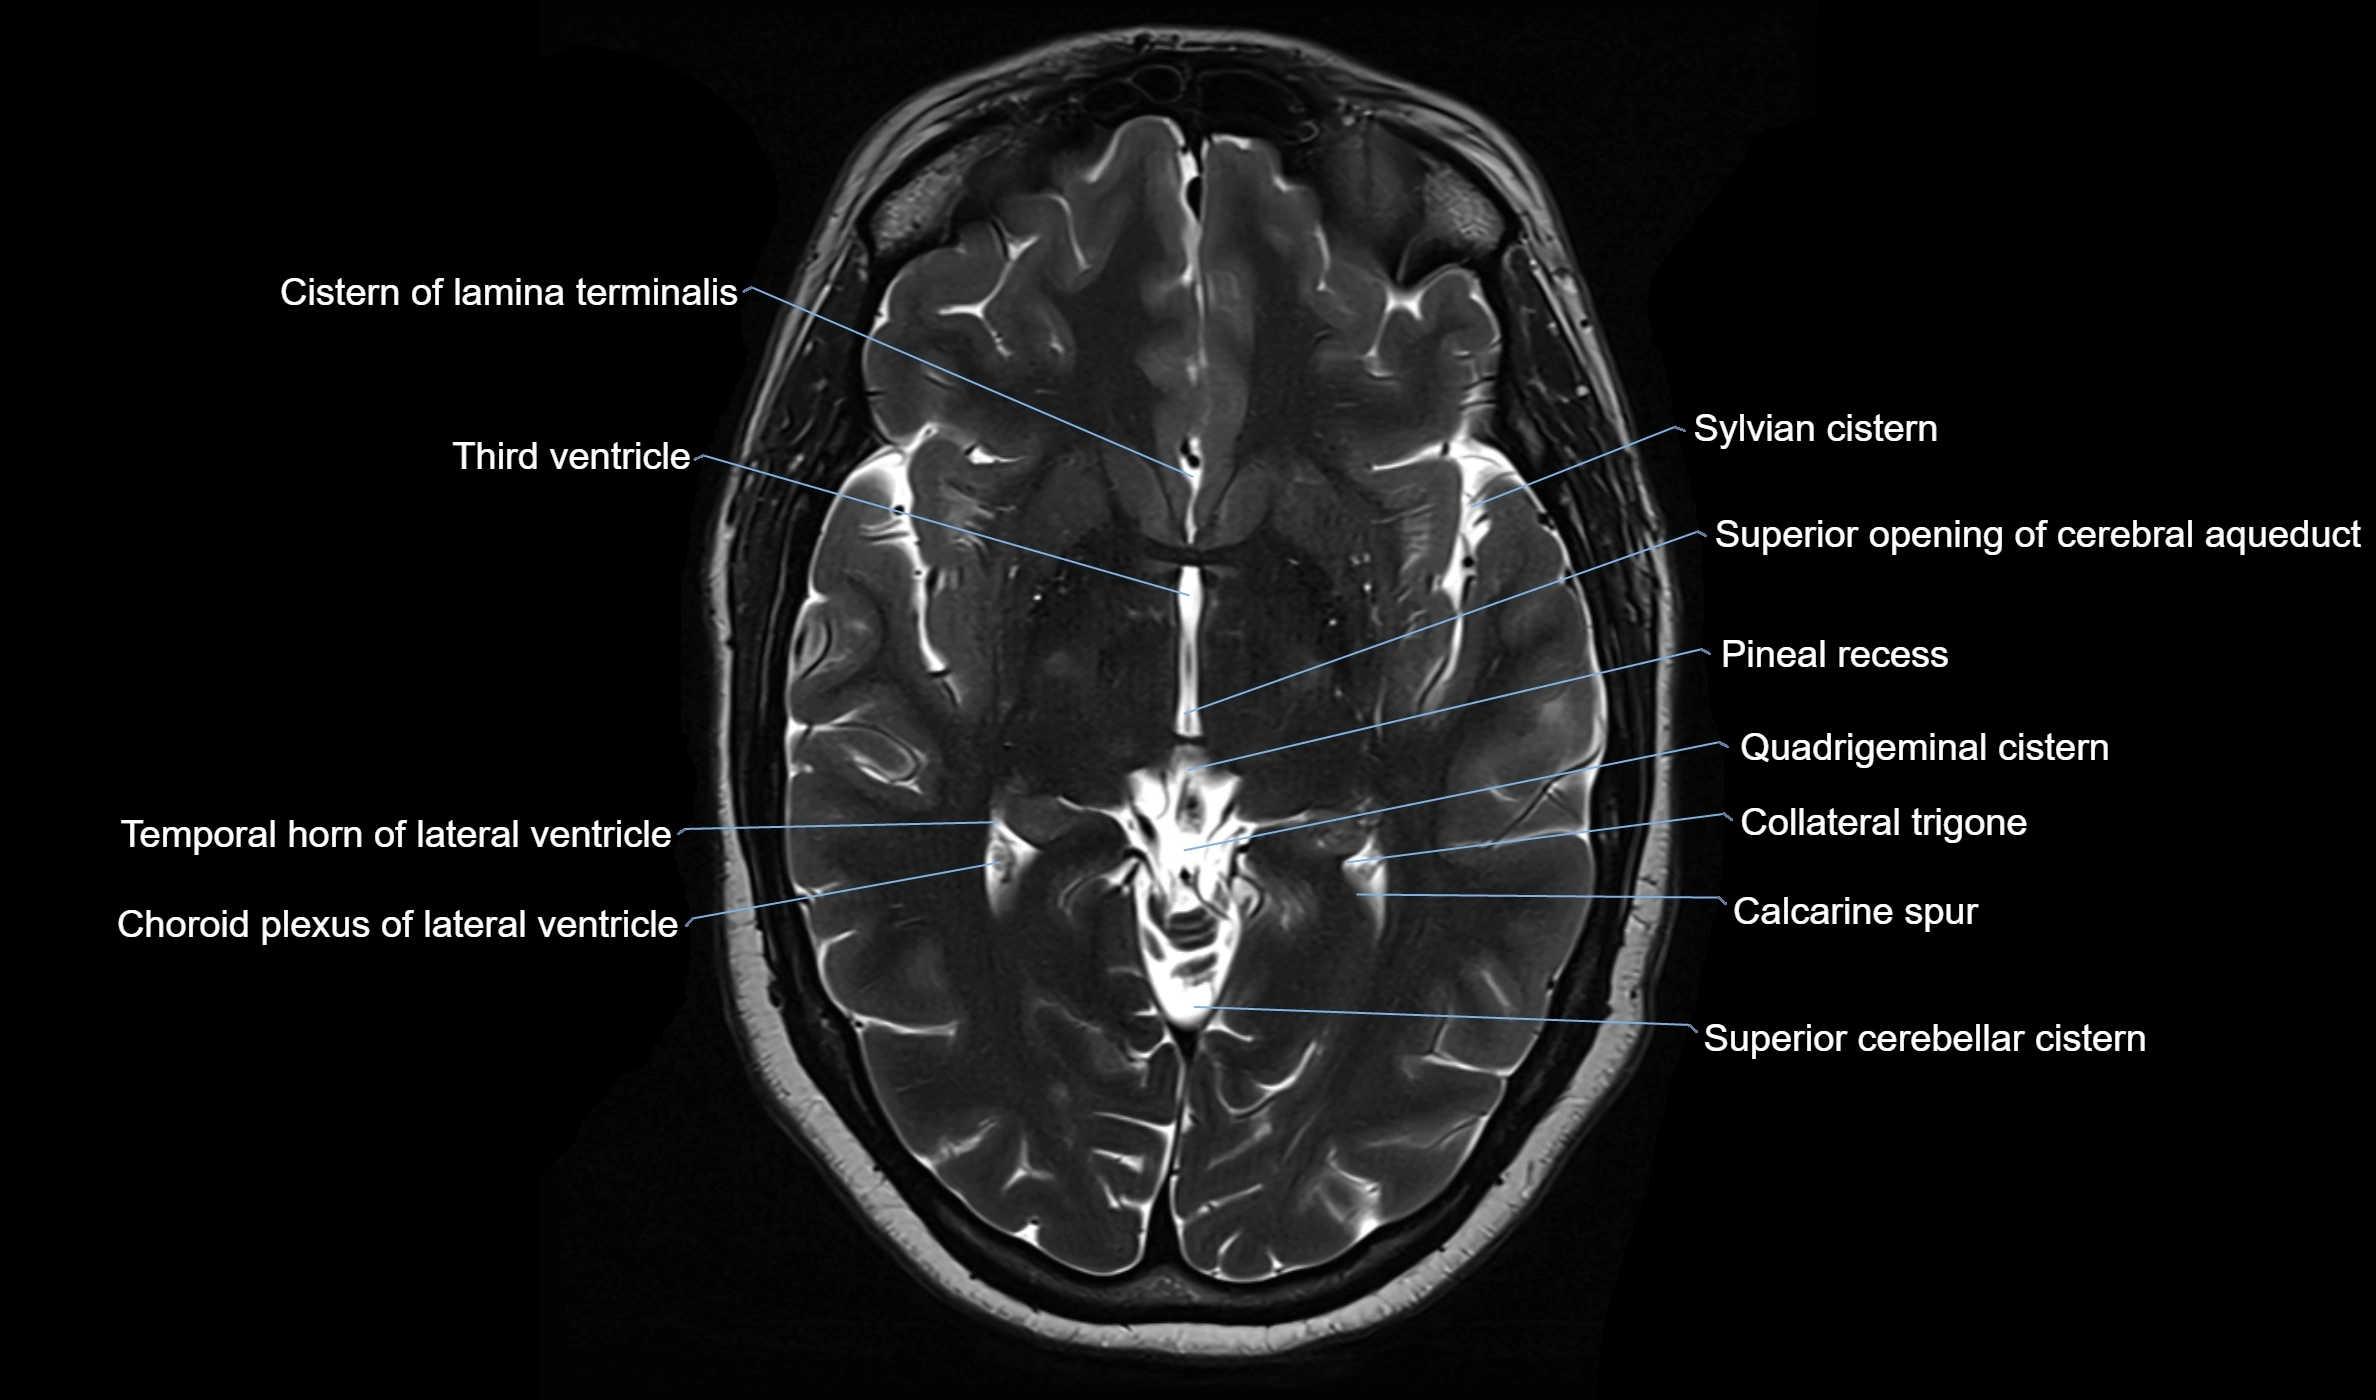

MRI images

image